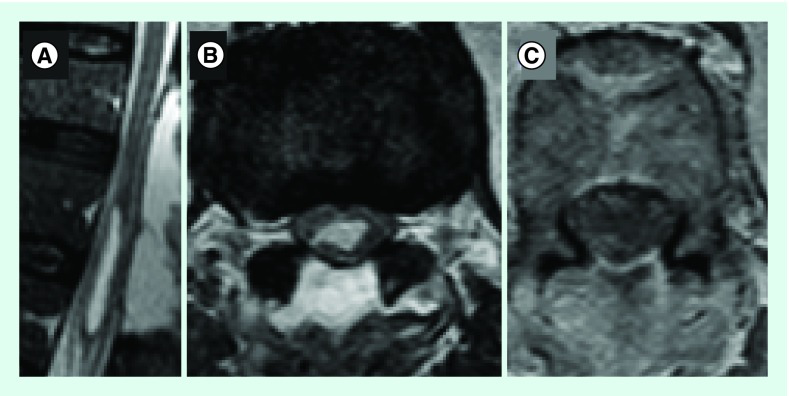

术后,导尿管被保留在原位,以保持感觉。病人在术后7天出院,没有进一步的事件,并转介到康复单位。术后1个月,成功拔除导尿管,无步态障碍,有轻度感觉障碍。术后MRI显示残余囊肿的肿块效应减弱(图2)。神经病理学检查发现一个低细胞的囊性肿瘤,显示双较性星形细胞成分和长而细的突起。未诱发间变性特征,增殖指数(Ki67)小于1%。ATRX和IDH1未发生突变,BRAF存在易位。对PA进行诊断(图3)。

图2。T2矢状图(A), T2轴向图(B)和T1 gad后轴向图(C)显示囊性病变肿块减轻,钆感染后没有造影剂摄取。